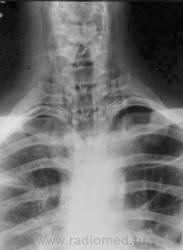

Молодой человек получил удар в шею. Был доставлен в травмпункт, дан барий для исключения перфорации пищевода.

Перфорации похоже нет, но есть другое...

Это чем же его ударили? Я так понимаю, ограниченный пневмоторакс слева  + эмфизема мягких тканей шеи?

Шейный кифоз настораживает.Отсутствие легочного рисунка в верхней доле левого легкого с краем легкогоЭмфизема мягких тканей шеи..Согласна с коллегой.Пару лет назад по кифозу ШОП, увеличению превертебрального пространства и столбу воздуха поставили разрыв пищевода.Дали  контраст-подтвердили.

Затекания контраста за пределы пищевода на представленных рентгенограммах не выявлено. Нет фазы тугого заполнения. Левосторонний пневмоторакс.

Да, ЛОРа 100% надо на консультацию, т.к. барий затек не туда.